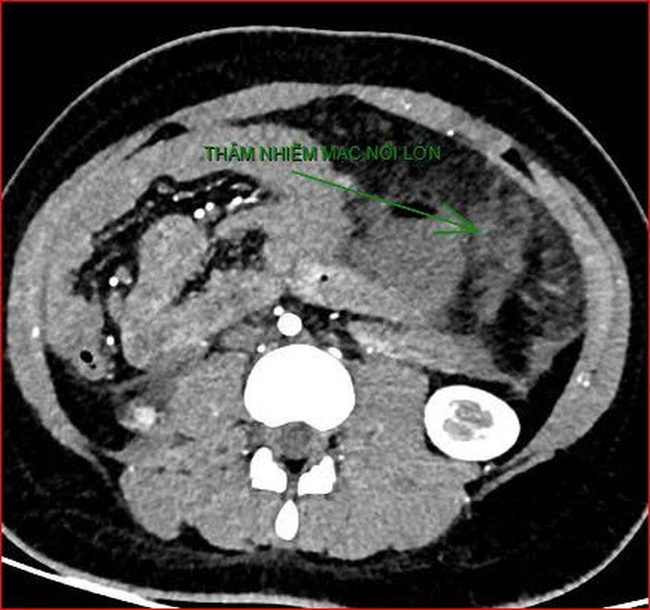

Khoảng 21h40, kết quả chụp CT cho thấy bệnh nhân rơi vào tình trạng cực kỳ nặng và hiếm gặp, bao gồm: Xoắn dạ dày, nhồi máu thận trái, nhồi máu lách, viêm đầu tụy, viêm hỗng tràng, kèm dịch ổ bụng và tràn dịch màng phổi, trên nền bệnh nhân mắc hội chứng Down và tim bẩm sinh.

kết quả chụp CT cho thấy bệnh nhân rơi vào tình trạng cực kỳ nặng và hiếm gặp.